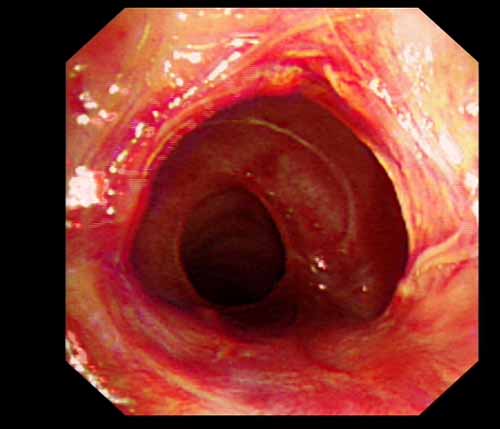

患者李某某,女,45歲,因氣管插管咳嗽、喘憋10天入院。頸部CT檢查示聲門下約20mm處氣管明顯狹窄,狹窄段長約26mm,最窄處直徑約4.4mm。支氣管鏡檢查見聲門下約2cm氣管呈漏斗狀縮窄,直徑約4-5mm,支氣管鏡無法通過。經科室討論,決定行電子支氣管鏡下氣管球囊擴張治療。與患者及家屬充分溝通并經三方見證談話簽署知情同意書后,在患者持續吸氧、局麻下,科主任于世倫主任醫師帶領治療小組為患者實行電子支氣管鏡下氣管球囊擴張術。手術過程順利,出血量很少,術后患者呼吸困難癥狀即可明顯緩解。10天后行二次擴張,患者日常活動無明顯喘憋,二次術后5天出院。

支氣管球囊擴張術始于1984年,Coken等首先報道1例4~5個月新生兒,因肺葉手術導致支氣管吻合口瘢痕狹窄,在硬質氣管鏡下采用球囊擴張治療并獲得成功,此后,采用球囊擴張術治療支氣管肺癌或其他原因引起的氣道狹窄報道逐漸增多,直到1991年,采用支氣管鏡行氣道球囊擴張術廣泛應用于臨床,大大減輕了患者痛苦。球囊擴張術主要用于氣管、主支氣管或葉支氣管狹窄的擴張治療,主要病因包括:良、惡性腫瘤所致外壓性狹窄,支氣管結核致氣道狹窄,氣管插管、氣管切開后致氣管瘢痕狹窄,支氣管異物取出后瘢痕狹窄,肺葉切除術后吻合口狹窄,其他原因所致氣道狹窄。電子支氣管鏡下氣管球囊擴張術的成功開展,極大地提升了我院呼吸系統疾病的診治水平,填補了棗莊地區在此技術上的空白,為良性氣道狹窄的治療開辟了一條新的途徑,標志著我院呼吸內鏡介入治療技術又邁上了新的臺階。

術前聲門下的漏斗樣狹窄口 術中球囊擴張 術后擴張開的氣管管腔